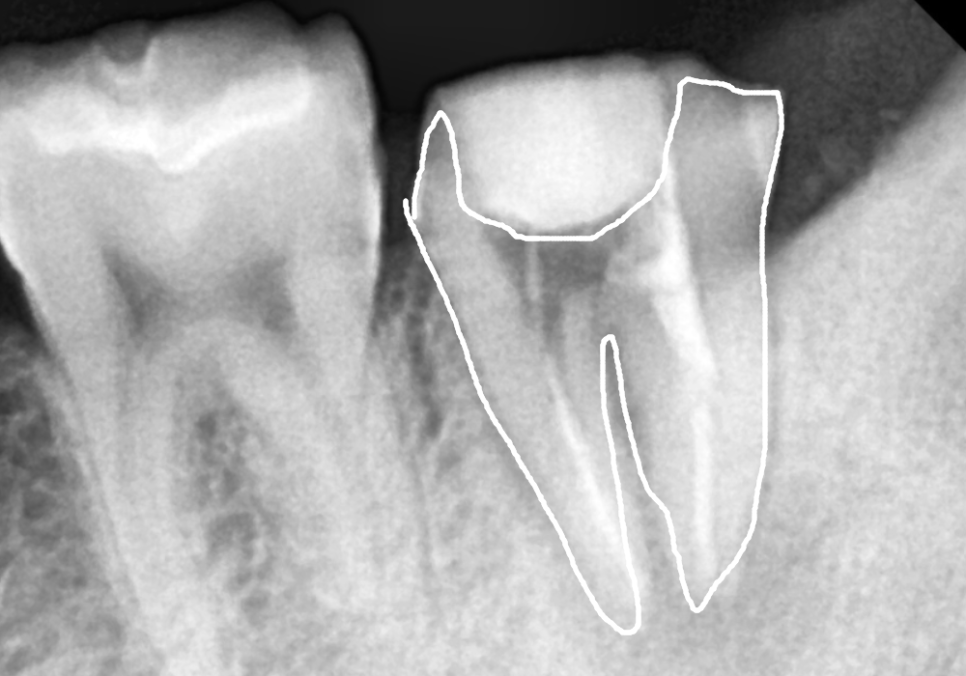

치료를 위해 보철물을 벗겨냈는데,,

예전 충치가 심했는지 남은 치아가 별로 없네요.

기존에 채워져 있던

오래된 충전물을 말끔히 제거한 뒤,

여러 차례 정밀한 소독 과정을 거쳤습니다.